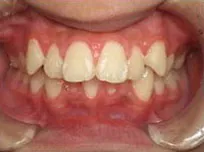

以下、当院で実施した床矯正の症例となります。

症例1

| 治療期間 | 11ヶ月(2021年6月〜2022年5月) |

| 費用 | 495,000円(税込) |

| リスクや副作用 | 成長期が終わった18歳以降に、2期矯正が必要になることがある |